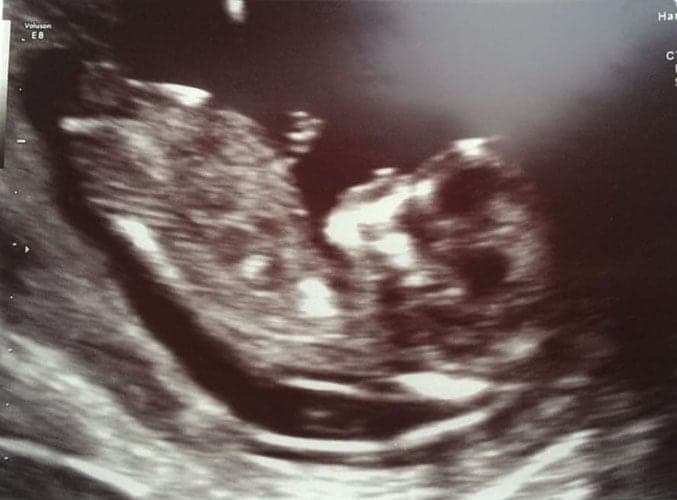

Ultraschallbilder aus dem 2. Trimester (13. bis 28. SSW)

Im 2. Trimester bekommt man oft die schönsten „Ganz-Körper“ Ultraschallbilder. Das Baby ist nun so groß, dass man alles gut erkennen kann und noch nicht zu groß, so dass es noch ganz auf das Bild passt. In dieser Zeit lässt sich meist das Geschlecht bestimmen, wobei manche Babys es einfach nicht preis geben wollen und sich immer so drehen, dass man nichts erkennen kann.